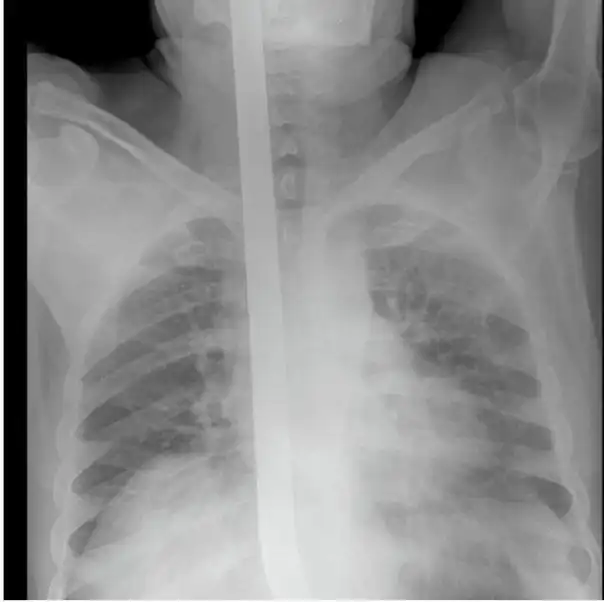

Мужчина упал на лом не повредив жизненно важных органов, говорят после операции выписан в удовлетворительном состоянии домой.